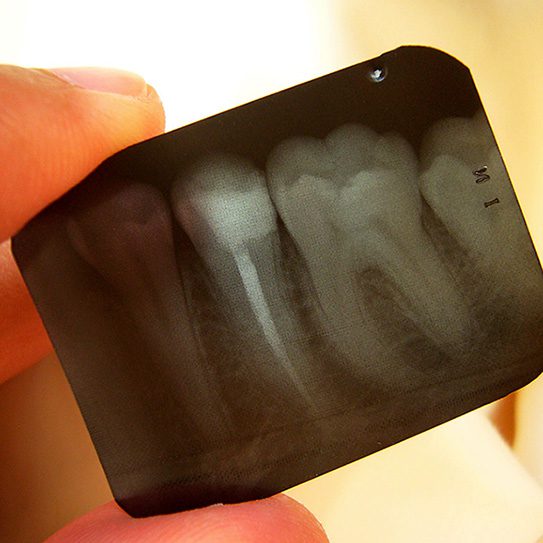

Dental X-Rays Help Spot Problems Early

X-rays have become an incredibly valuable tool in modern medicine—especially for dentistry! We learn a lot from visually examining your teeth, but not everything is visible to the naked eye during a routine dental exam. Dental X-rays allow us to detect and diagnose tooth decay between teeth, on hard-to-reach surfaces, and under existing dental work. X-rays can even be helpful in identifying dental and orthodontic issues that exist beneath the gum line—something that was impossible without invasive procedures before X-rays became widely available.